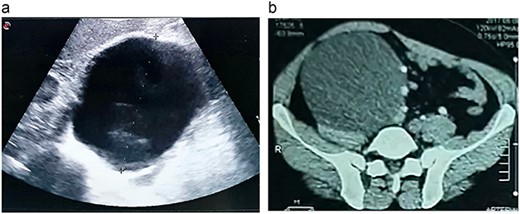

A 46-year-old male presented with mild abdominal pain for the last 2 months. The pain was generalized, recurrent and did not relieve on medication. The patient showed intermittent claudication in his right leg. He presented with a similar complaint five years ago; abdominal pain and urinary urgency and hesitancy, which led to a diagnosis of a simple abdominal cyst. Past medical history was insignificant. Surgical history included retroperitoneal cystectomy, herniorrhaphy and a cleft palate repair. Patient had no other complaints and was not on any medications. He was a smoker with a 22 pack-year smoking history. His temperature was normal, and there was no history of weight loss or loss of appetite or change in bowel movement. On physical examination, the abdomen was soft and non-tender without distention. There was a palpable mass in his right flank. Vital signs and blood tests were within normal limits. Abdominal ultrasound (US) showed a large fluid-filled cystic lesion (Fig. 1a). Subsequent computerized tomography (CT) of the abdomen showed a large, well-defined, clear fluid-filled cyst measuring 17 × 11 × 10 cm, located in the retroperitoneum abutting the lower half of the right kidney, extending to the pelvis and compressing the inferior vena cava (Fig. 1b). Patient was cleared for surgery. Surgical exploration showed several adhesions surrounding the cyst. The cyst was partially isolated from the right ureter and iliac vein and artery (Fig. 2a and b), then surgical excision of 90% of the cyst was performed (Fig. 3). Histopathological report found the cystic wall composed of fibrous connective tissue and lined by one layer of flat cells, with mild lymphocytic infiltrate and congested blood vessels confirming the diagnosis of a chylolymphatic cyst (Fig. 4). On a 1-year follow-up, the patient appears to be recovered and in good health with no recurrence.

a. An US image showing a large cystic mass in the right abdomen. b. A CT scan of the abdomen showing a cystic mass of 17 × 11 × 10 cm with a fat-fluid level.